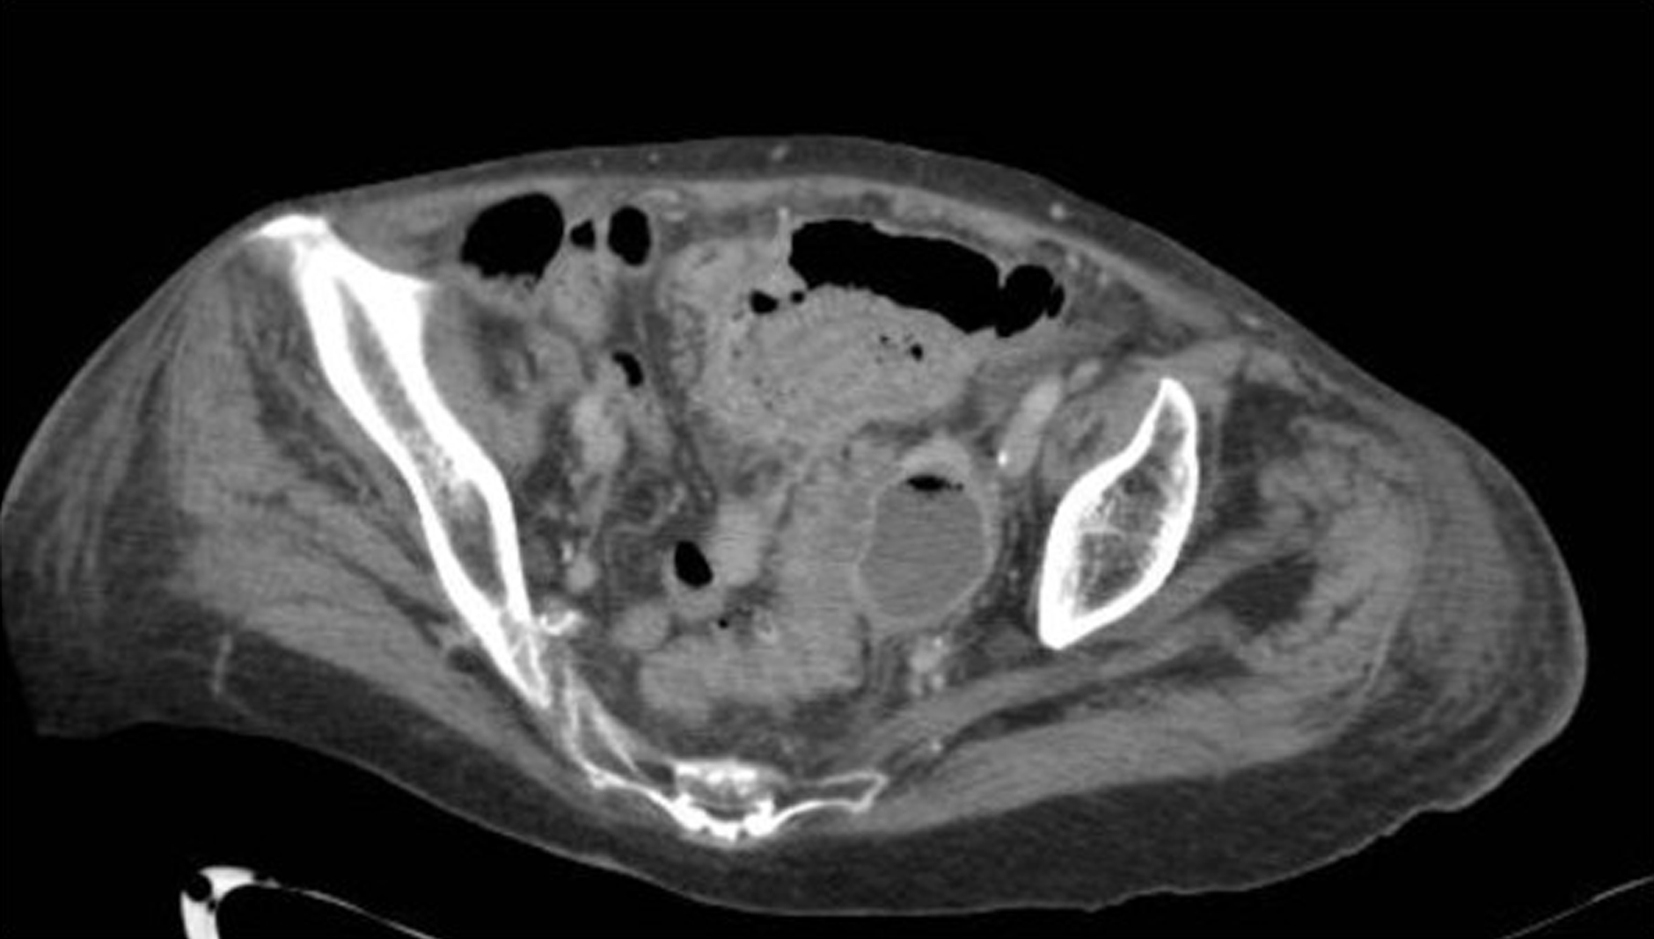

Abdominal CT has become the standard of care for diagnosing diverticulitis. A CT without contrast can identify the presence of diverticular disease. CT with intravenous (IV) contrast is commonly used to assess for diverticulitis. However, CT with both IV and enteric (either oral or rectal) contrast is the ideal method to assess for diverticulitis and any associated complications, with 98% sensitivity and 99% specificity. CT findings may include colonic wall thickening, pericolonic fat stranding, localized perforation (also known as micro-perforation), abscesses, as well as free air or fluid ( Figs. 81.1–81.3 ). While generally outside the scope of ED practice, the Hinchey staging system can be used to stratify diverticulitis based on the level of abscess formation or perforation ( Box 81.4 ).

Computed Tomography Imaging Illustrating Diverticulitis With Free Air Formation as a Result of Perforation.

From Sartelli M, Moore FA, et al. A proposal for a CT driven classification of left colon acute diverticulitis. World J. Emerg Surg . 2015;10(3):1–11, Fig. 5.